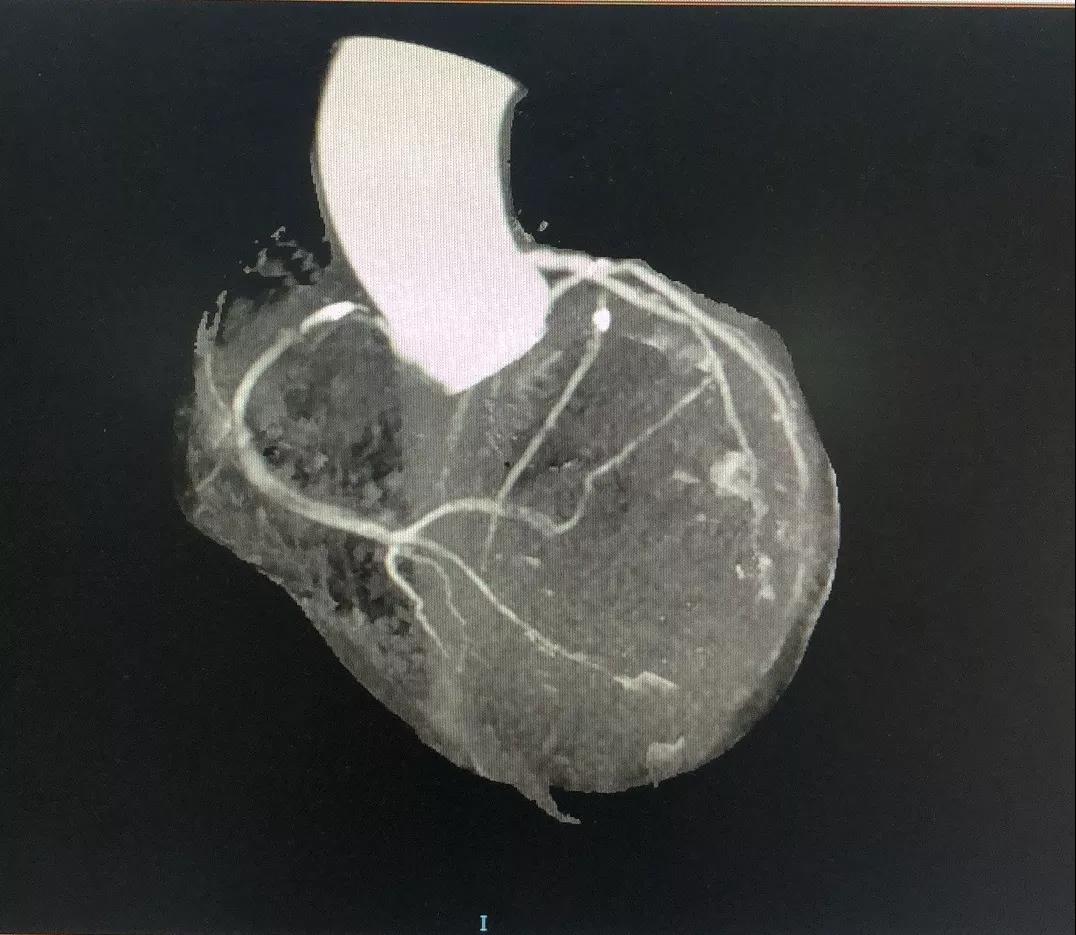

关于LCX

LCX CTA特点:

1、LCX血管相对比较“健康”;

2、LCX近中段发出比较粗大的侧枝逆向供应右冠左室后支,侧枝血管仅轻度扭曲;

3、LM前分叉相对“健康”。

有了上述信息,结合冠脉造影资料,逆向开通RCA就有了一根条件相对比较好的侧枝血管。